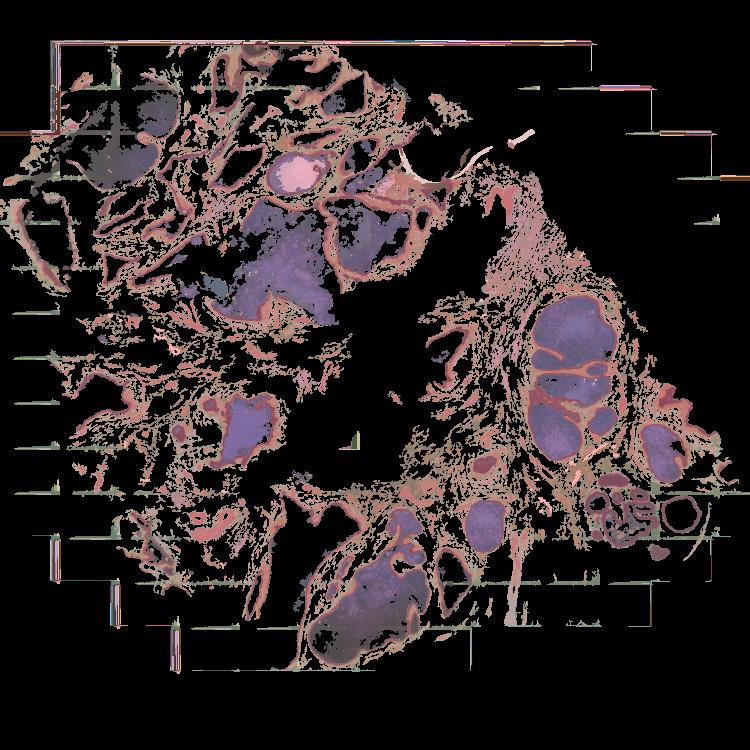

To study the spatial interactions among cancer and non-cancer cells1, we here examined a cohort of 131 tumour sections from 78 cases across 6 cancer types by Visium spatial transcriptomics (ST). This was combined with 48 matched single-nucleus RNA sequencing samples and 22 matched co-detection by indexing (CODEX) samples. To describe tumour structures and habitats, we defined ‘tumour microregions’ as spatially distinct cancer cell clusters separated by stromal components. They varied in size and density among cancer types, with the largest microregions observed in metastatic samples. We further grouped microregions with shared genetic alterations into ‘spatial subclones’. Thirty five tumour sections exhibited subclonal structures. Spatial subclones with distinct copy number variations and mutations displayed differential oncogenic activities. We identified increased metabolic activity at the centre and increased antigen presentation along the leading edges of microregions. We also observed variable T cell infiltrations within microregions and macrophages predominantly residing at tumour boundaries. We reconstructed 3D tumour structures by co-registering 48 serial ST sections from 16 samples, which provided insights into the spatial organization and heterogeneity of tumours. Additionally, using an unsupervised deep-learning algorithm and integrating ST and CODEX data, we identified both immune hot and cold neighbourhoods and enhanced immune exhaustion markers surrounding the 3D subclones. These findings contribute to the understanding of spatial tumour evolution through interactions with the local microenvironment in 2D and 3D space, providing valuable insights into tumour biology.